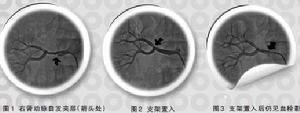

2008年韓國醫生為1例腎動脈自髮夾層致腎臟梗死患者進行了導管內直接溶栓聯合支架置入。2009年中國醫學科學院阜外心血管病醫院高血壓中心 黑龍江省牡丹江市心血管病醫院的一例患者接受支架置入聯合尿激酶導管內溶栓,血管再通滿意,術後口服華法林抗凝治療。2002年美國聖迭戈醫學中心曾對自發性腎動脈夾層的抗凝療效進行研究,結果顯示,患者服用華法林抗凝的短期療效更佳,但該研究未追蹤觀察該藥的遠期療效,故本例患者的預後值得進一步隨訪。